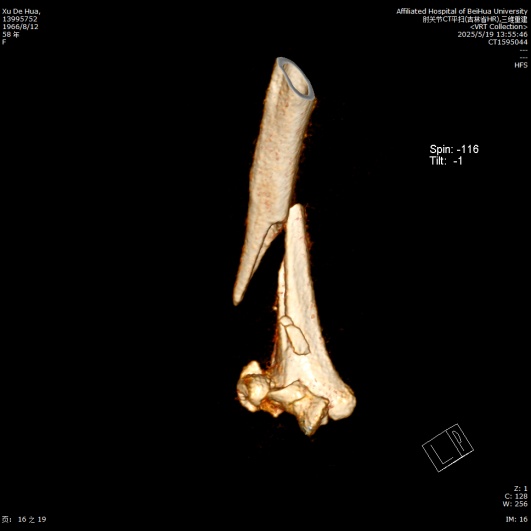

待麻醉生效后,患者取左侧卧位于手术台上,右上肢术区常规消毒,铺无菌单,贴皮肤保护膜。取右上臂中远段后正中入路,纵行切开一长约18.0 cm手术切口,依次切开皮肤、皮下,切开筋膜层,充分显露尺骨鹰嘴,将尺神经分离充分显露后予以保护,应用微型摆锯“V”形截骨尺骨鹰嘴,将尺骨鹰嘴连同肱三头肌腱剥离,湿盐水纱布保护,注意保护桡神经,暴露肱骨中远段,见肱骨中下段螺旋形骨折,分离短缩移位,肱骨滑车、肱骨小头、肱骨内外髁多处骨折线,分离旋转移位,局部骨质缺损,将肱骨中下段、肱骨滑车、肱骨小头、肱骨内外髁骨折复位,克氏针临时固定,后分别于右肱骨远折端内侧、后侧铺放2枚解剖型钢板,注意保护桡神经和尺神经,拧入数枚螺钉固定,C臂透视见钢板及螺钉长度及位置满意(见图2)。并于外髁骨缺损处植入3.0 g β-磷酸钙生物陶瓷不规则颗粒。将截断的尺骨鹰嘴复位后打入两根克氏针临时固定,并应用钢丝“8”字捆绑固定(见图3),活动肘关节,见骨折复位固定确实,关节无异响和绞索。后将尺神经松解前置,见神经松紧带适宜。后清点器械、纱布无误后,冲洗术区,彻底止血,术区留置负压引流管1枚,撒入盐酸万古霉素0.5 g及止血粉于切口内,预防感染及促进止血,应用可吸收性倒刺线2根逐层缝合肌层及皮下,一次性使用皮肤缝合器关闭切口,无菌敷料进行外包扎,石膏托固定肘关节于功能位(90˚屈曲),术毕。手术经过顺利,麻醉效果满意,术中出血量约1200 ml,给予输注ABO血型AB型Rh(D)阳性去白细胞悬浮红细胞2单位,过程中无明显输血不良反应,术后患者呈清醒状态安返病房。

Figure 2. Intraoperative findings and C-arm fluoroscopy with anteroposterior and lateral radiographs

2. 术中外相及C型臂透视正侧位X线片